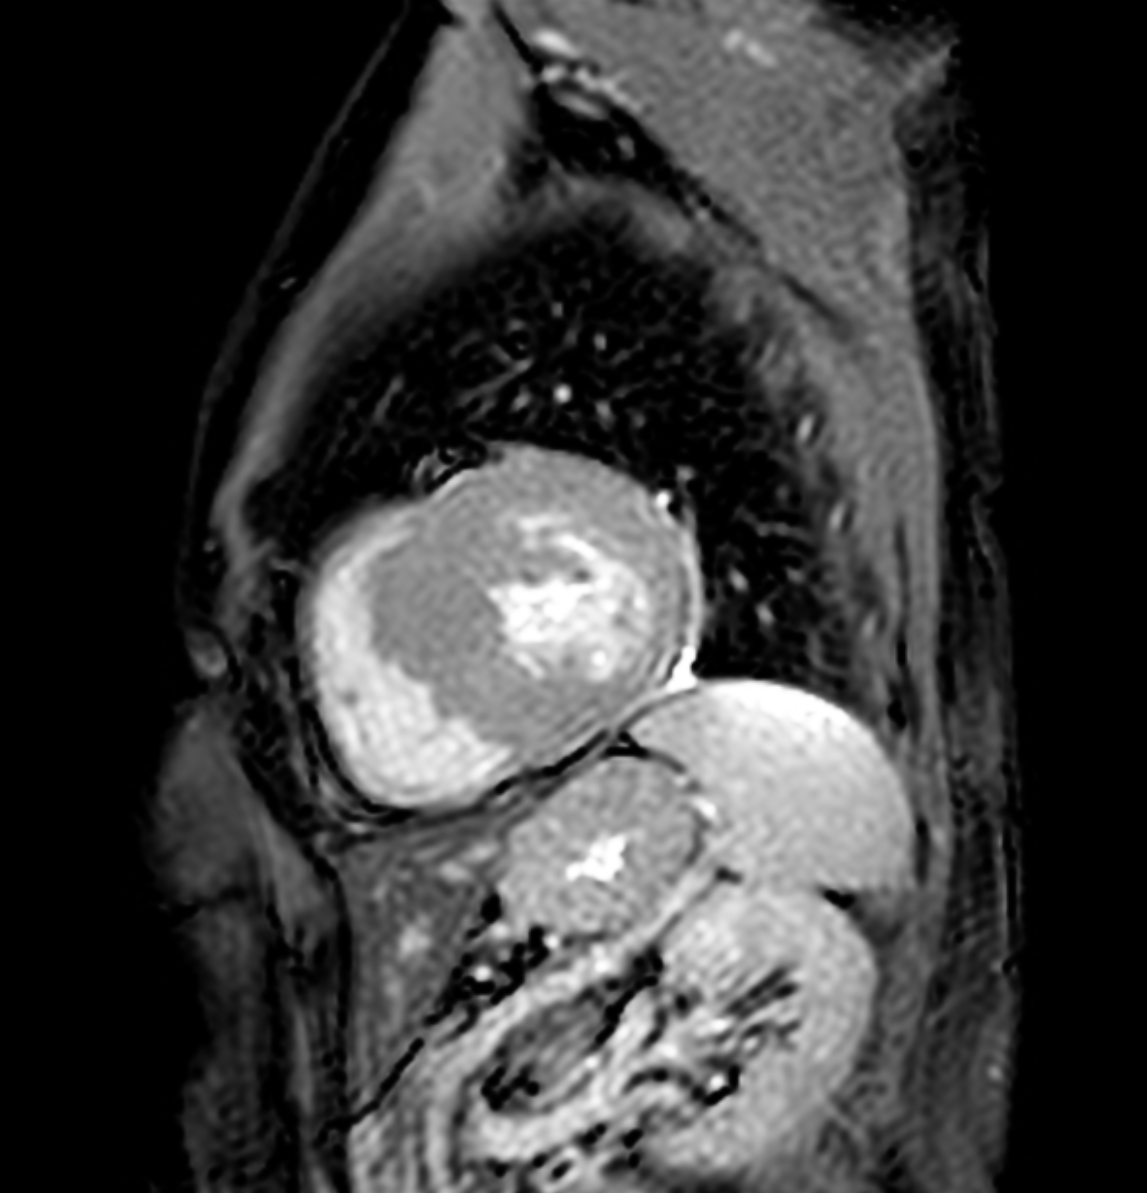

Clinical Case [Uncaptioned image] [Uncaptioned image]

Image Findings: The patient underwent contrast-enhanced computed tomography which showed features of a congested liver with flip-flop pattern of enhancement. Hepatic veins show hypoattenuation on delayed phase. An accessory hepatic vein is also noted in segment VI. A diagnosis of Budd Chiari syndrome (BCS) was made on the basis of the clinical and imaging features. The patient was referred to the interventional radiology team for an endovascular rescue. On conventional venogram, the diagnosis of BCS was confirmed as the hepatic veins were thrombosed. An accessory segment VI hepatic vein was noted draining into the IVC…

Title: Accessory right inferior hepatic vein [Uncaptioned image] [Uncaptioned image]

Discussion:Marked dilatation of the pulmonary trunk (6.7 cm) with the right (5.4 cm) and left (4 cm) main branches. Lung window shows mild bilateral diffuse faint groundglass centrilobular lung nodules that may reflect an underlying infection. Scans through the upper abdomen revealed average size cirrhotic liver and reflux of contrast into the IVC and hepatic veins with Incidental opacification of accessory right inferior hepatic vein…